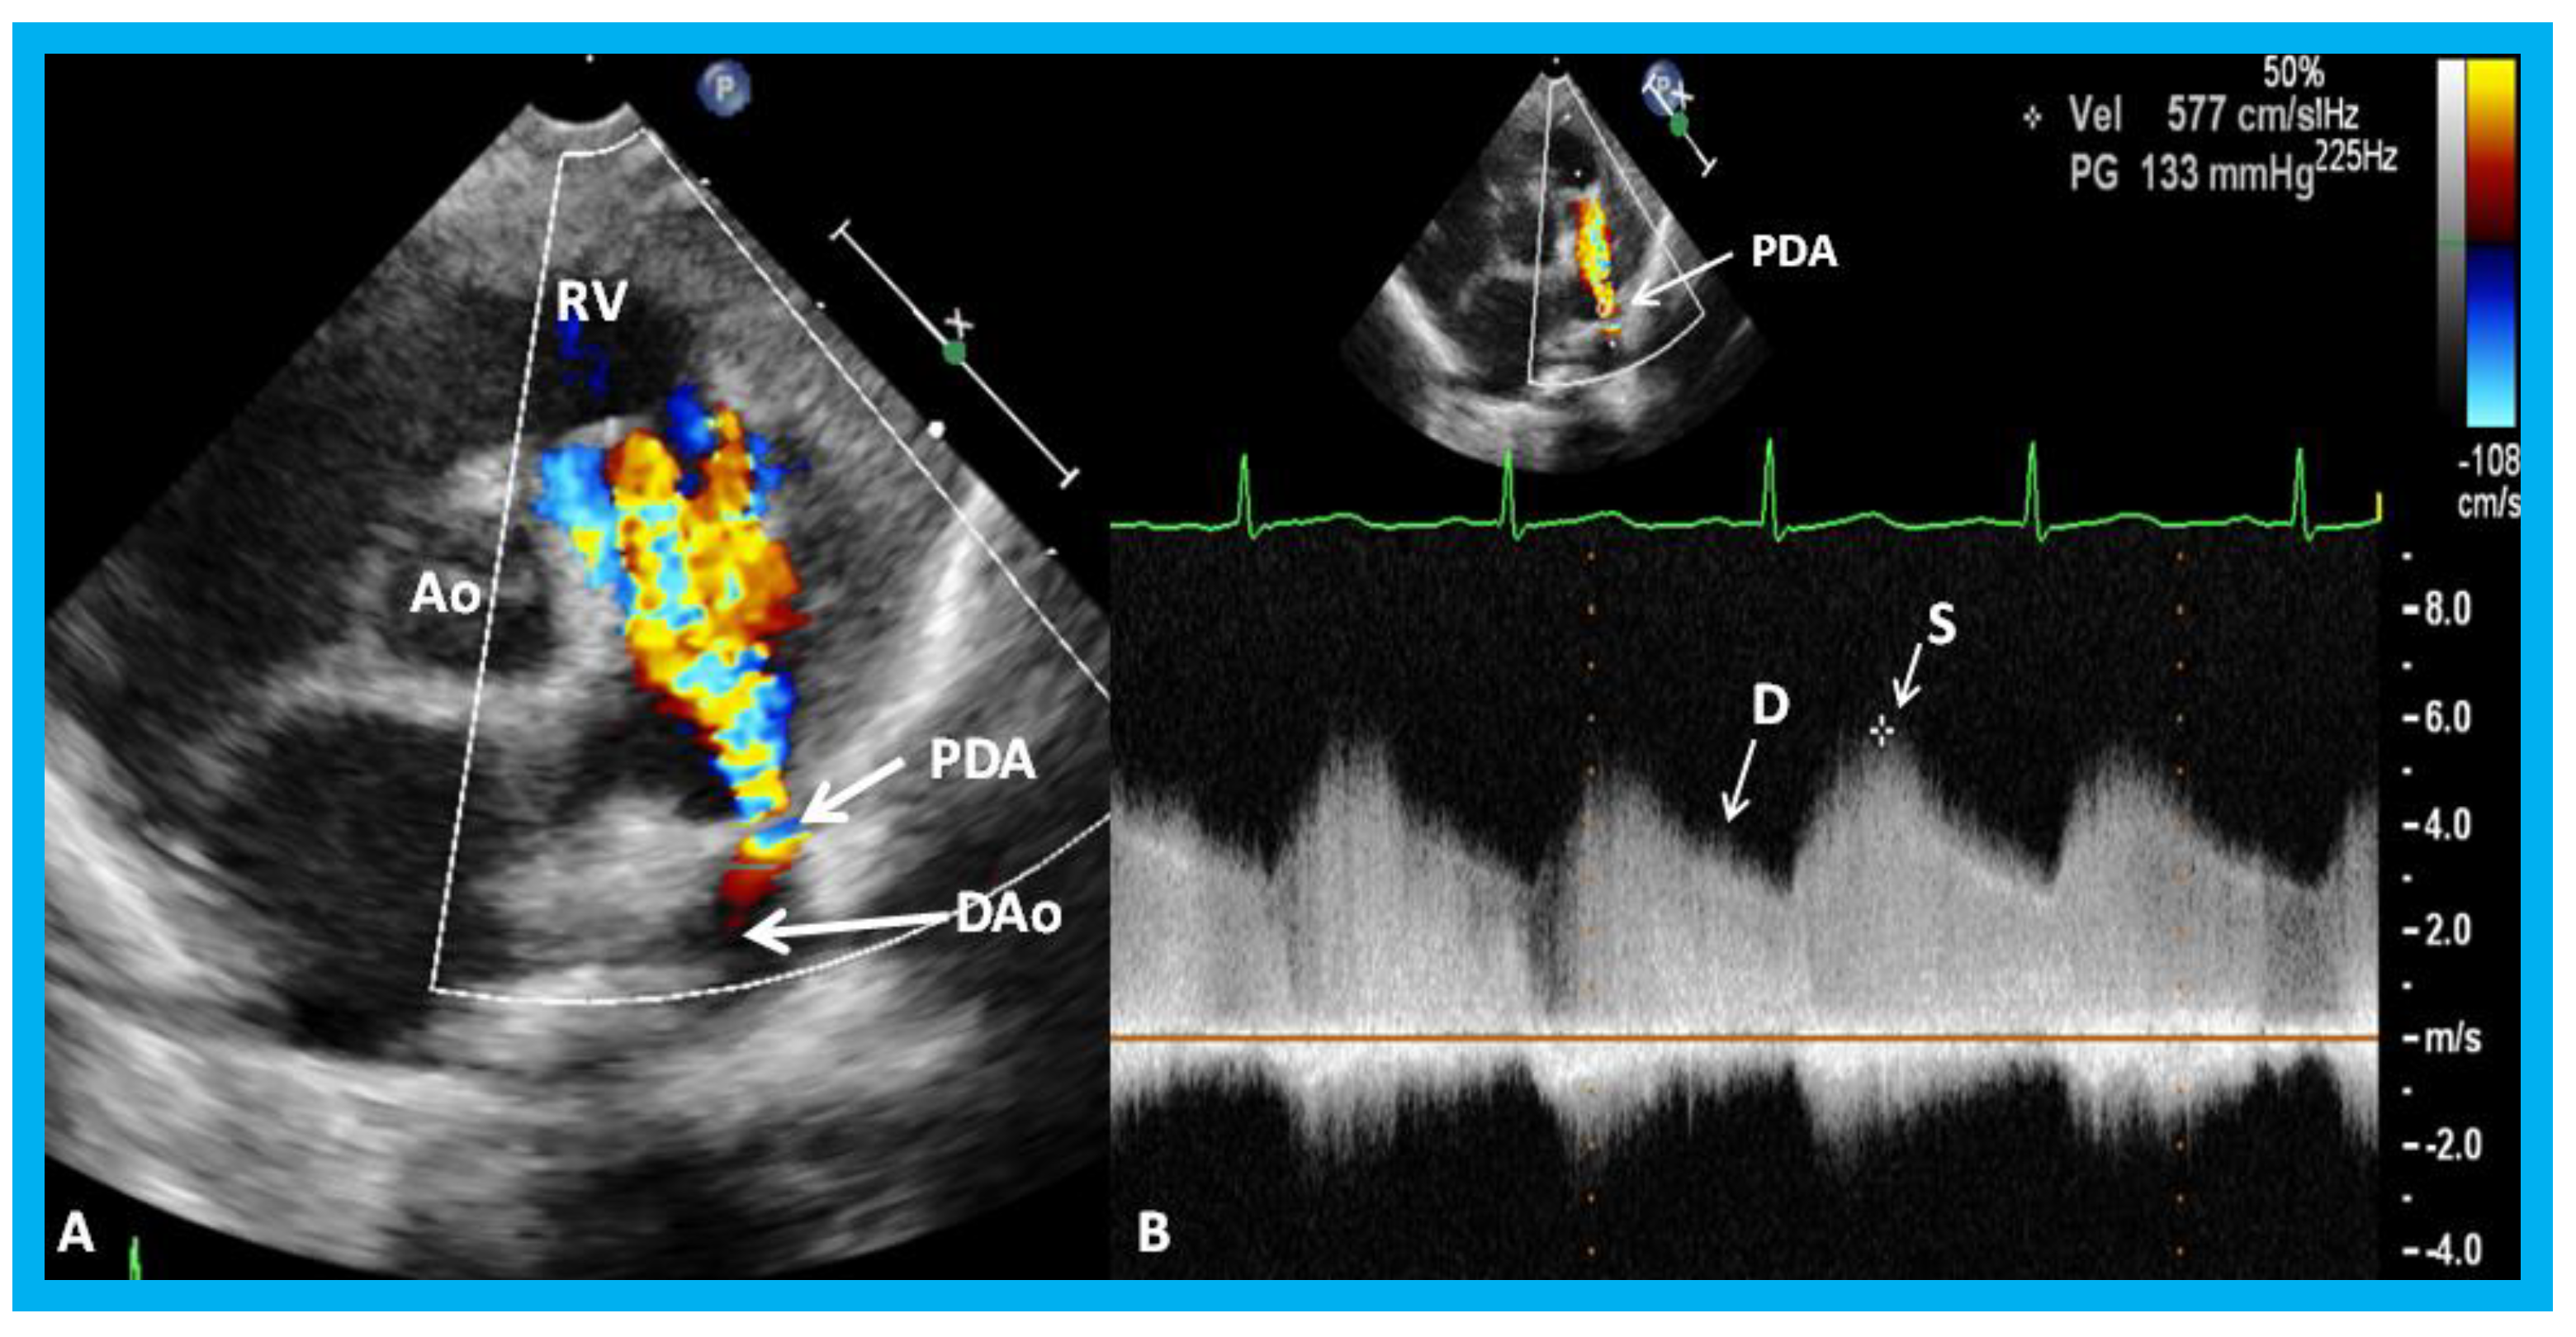

Frontiers Echocardiographic Evaluation of Patent Ductus Arteriosus in Pda Evaluation By Echo Parasternal long axis pulmonary valve: Concurrently, advances in diagnostic echocardiography and the widespread availability of echocardiography have resulted in improved detection and. Echocardiography (echo) with color flow doppler is considered as the gold standard to identify a hemodynamic patent. This paper focuses on echocardiographic evaluation of pda in the preterm infant and particularly on the. Important views for transthoracic echocardiography. Pda Evaluation By Echo.

EchoDoppler study in the parasternal shortaxis projection Pda Evaluation By Echo Echocardiography (echo) with color flow doppler is considered as the gold standard to identify a hemodynamic patent. This view allows for 2d measurement of the pda at the. A pda shunt have an. Echocardiographic diagnosis and hemodynamic evaluation of patent ductus arteriosus in extremely low gestational age. Concurrently, advances in diagnostic echocardiography and the widespread availability of echocardiography have resulted. Pda Evaluation By Echo.